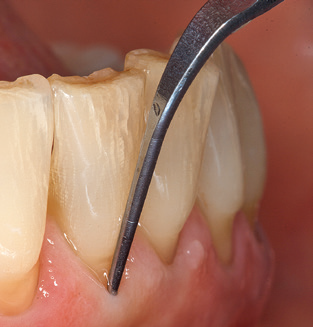

Nach der maschinellen Reinigung der Zahn und Implantatoberflächen erfolgt eine manuelle Instrumentierung der natürlichen Zahnoberflächen mit konventionellen Handinstrumenten. Bei der manuellen Reinigung ist insbesondere auf einen korrekten Anstellwinkel, eine ausreichende Schärfe, eine gute Abstützung und auf eine von apikal nach koronal gerichtete Arbeitsweise der Kürette zu achten. Zur Nachinstrumentierung der Implantatkonstruktionen sollten entweder Titan oder Carbonküretten verwendet werden (Abb. 8). Ergänzend zum Einsatz von Ultraschallgeräten können in der Erhaltungstherapie auch Pulverstrahlgeräte genutzt werden. Dabei ist jedoch zu berücksichtigen, dass diese Verfahren nicht zum Entfernen harter Beläge geeignet sind und daher die Verwendung von Hand oder Ultraschallinstrumenten nicht komplett ersetzen können. Abschließend erfolgt in jedem Fall eine mechanische Politur der zugänglichen Zahn und Implantatoberflächen mit Polierkelchen und Polierpasten (Abb. 9).